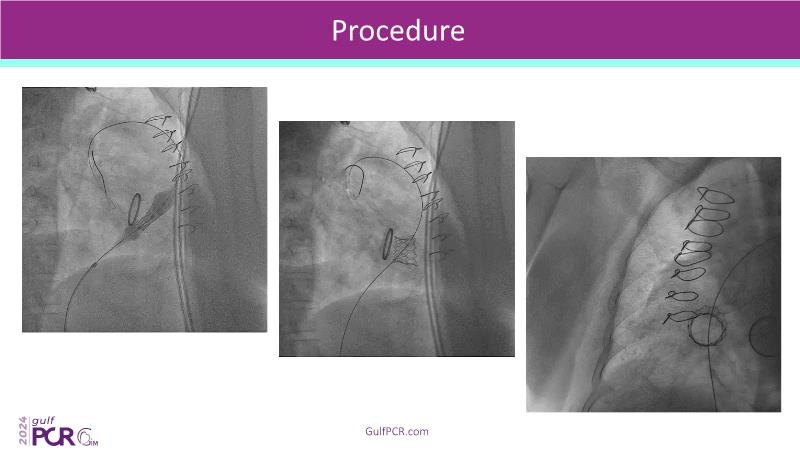

Stay ahead in TAVI innovation by exploring the advanced balloon-expandable Myval THV series. This session highlights the latest clinical data, optimal sizing and implantation techniques, and valuable real-world insights, including long-term follow-up results.

- To understand the best practices for Myval sizing and implantation technique for best outcomes

- To update on its experience and follow-up in "real-world" patient registries